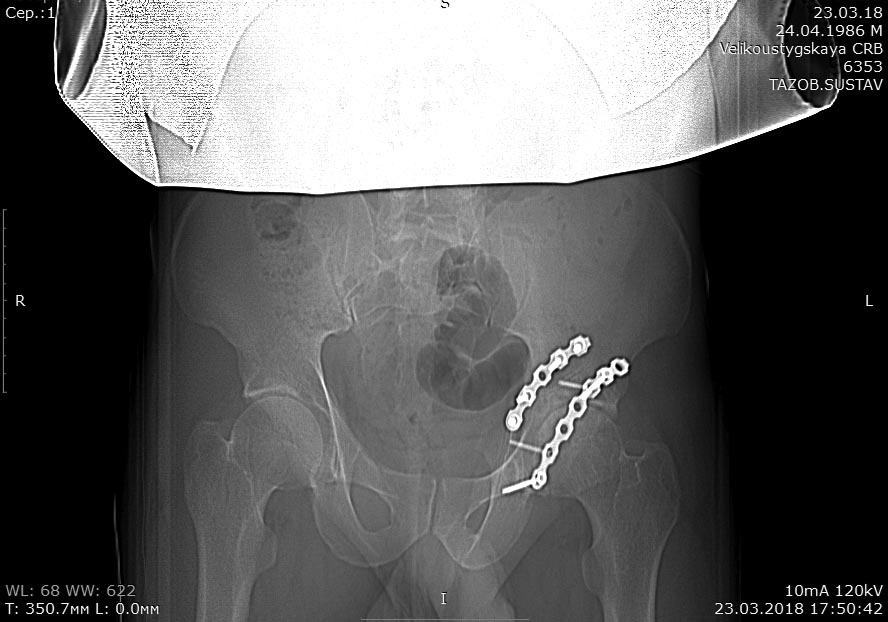

Травма в 2015 году. Водитель, попал в ДТП. Первично повреждение печени, перелом локтевой кости слева. Перелом задней колонный и задней стены левой вертлужной впадины. По экстренным показаниям выполнялась лапаротомия. Синтез задней колонны и задней стены через 13 дней через доступ Кохера-Лангенбека. Гладкий послеоперационный период. Выписан на амбулаторное лечение через 15 дней после операции. После выписки к нам не обращался, так как является жителем другого региона. Обратился через 2,5 года с жалобами на боли в области левого тазобедренного сустава.

На РКТ таза - перелом сросся. Отмечается кисты в области верхнего полюса головки бедра. Пластина фиксирующая задний край соприкасается с задними отделами головки бедра (видимо произошел частичный лизис костного края).